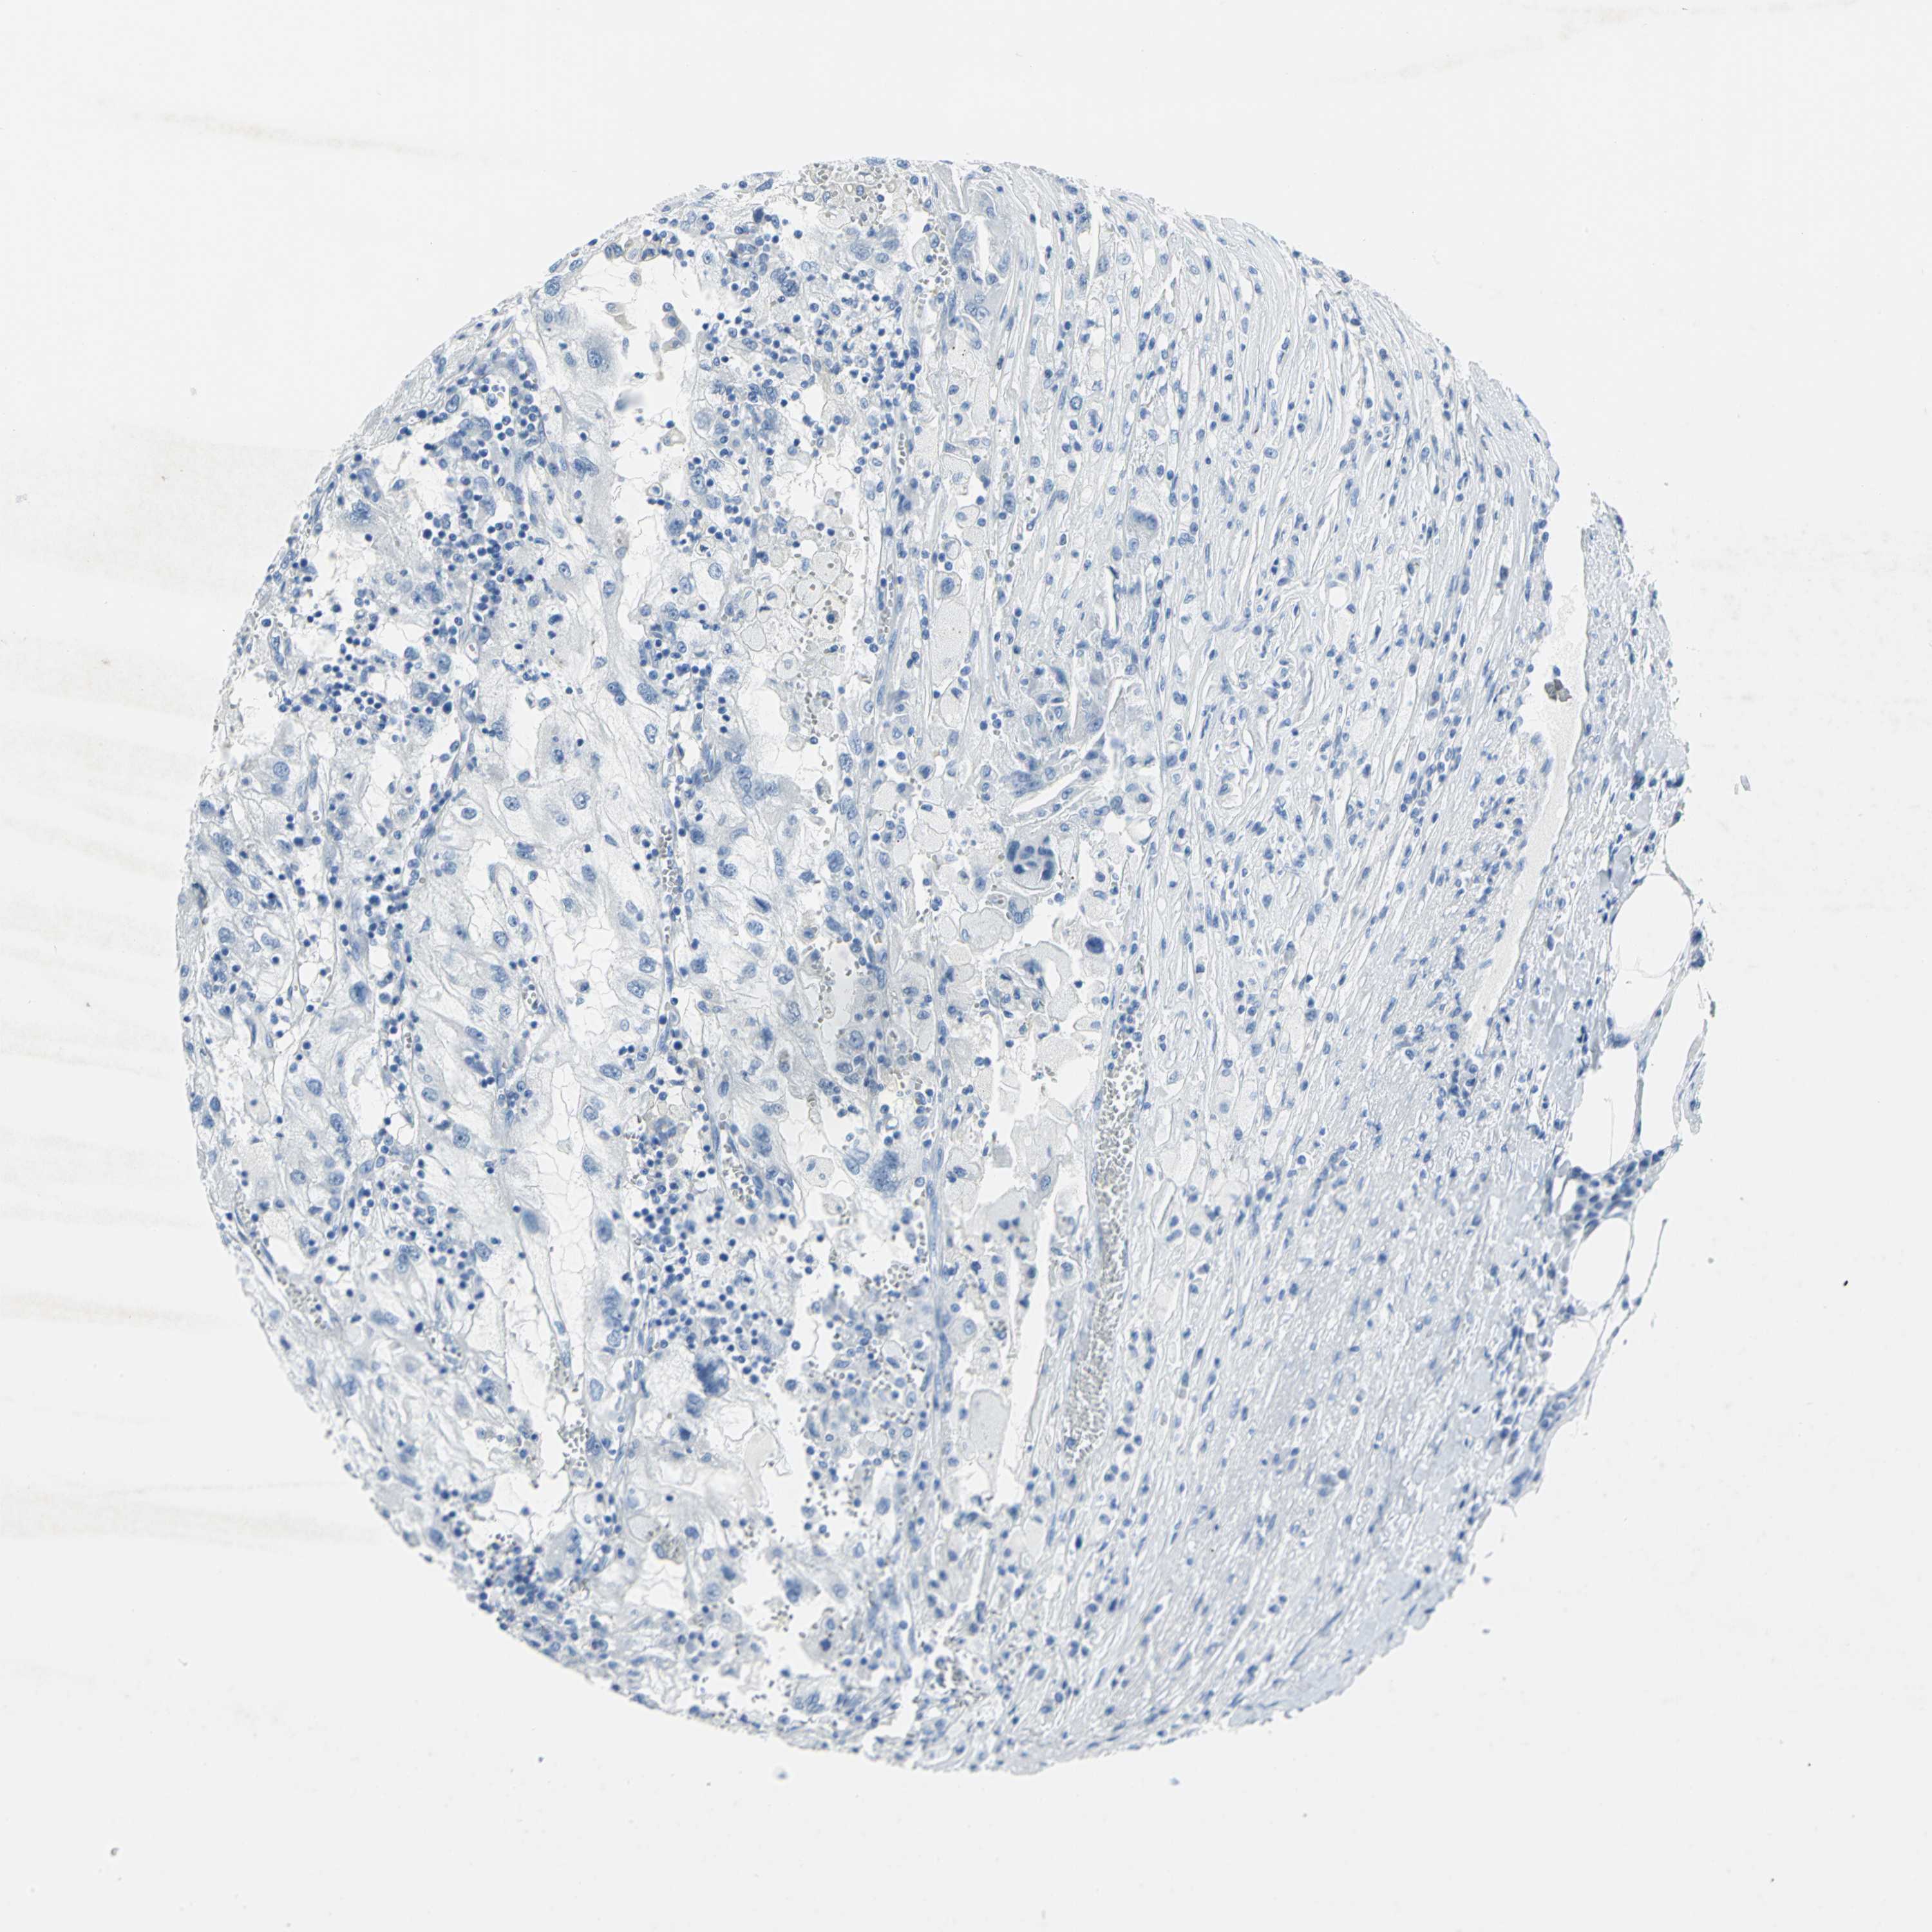

KIDNEY RENAL CLEAR CELL CARCINOMA (VALIDATION) - Interactive survival scatter ploti

The Survival Scatter plot shows the clinical status (i.e. dead or alive) for all individuals in the patient cohort, based on the same data that underlies the corresponding Kaplan-Meier plots. Patients that are alive at last time for follow-up are shown in blue and patients who have died during the study are shown in red.

The x-axis shows the expression levels (FPKM) of the investigated gene in the tumor tissue at the time of diagnosis. The y-axis shows the follow-up time after diagnosis (years). Both axes are complimented with kernel density curves demonstrating the data density over the axes. The top density plot shows the expression levels (FPKM) distribution among dead (red) and alive patients (blue). The right density plot shows the data density of the survived years of dead patients with high and low expression levels respectively, stratified using the cutoff indicated by the vertical dashed line through the Survival Scatter plot. This cutoff is automatically defined based on the FPKM cutoff that minimizes the p-score. The cutoff can be changed by dragging the vertical line or by entering a cutoff value in the square labeled "Current cut-off".

Under the Survival Scatter plot the p-score landscape (black curve; left axis) is shown together with dead median separation (red curve; right axis). Dead median separation is the difference in median mRNA expression between patients who have died with high and low expression, respectively. It is calculated as follows: median FPKM expression of dead patients with high expression - median FPKM expression of dead patients with low expression. This is intended to aid the user in visually exploring custom cutoffs and the associated p-scores and dead median separation.

Individual patient data is displayed and can be filtered by clicking on one or more of the category buttons on the top of the page. Categories describing expression level and patient information include: high, low, alive, dead, female, male and tumor stages. The scale of the x-axis can be toggled between linear and log-scale by clicking on the "x log" button. Mouse-over function shows TCGA ID, patient information and mRNA expression (FPKM) for each patient.

& Survival analysisi

Kaplan-Meier plots summarize results from analysis of correlation between mRNA expression level and patient survival. Patients were divided based on level of expression into one of the two groups "low" (under cut off) or "high" (over cut off). X-axis shows time for survival (years) and y-axis shows the probability of survival, where 1.0 corresponds to 100 percent.

SFN is not prognostic in Kidney Renal Clear Cell Carcinoma (validation)